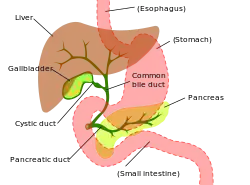

Digestive system diagram showing the bile duct | |

A bile duct is any of a number of long tube-like structures that carry bile, and is present in most vertebrates. The bile duct is separated into three main parts: the fundus (superior), the body (middle), and the neck (inferior).

Bile is required for the digestion of food and is secreted by the liver into passages that carry bile toward the hepatic duct. It joins the cystic duct (carrying bile to and from the gallbladder) to form the common bile duct which then opens into the intestine.

The top half of the common bile duct is associated with the liver, while the bottom half of the common bile duct is associated with the pancreas, through which it passes on its way to the intestine. It opens into the part of the intestine called the duodenum via the ampulla of Vater.

The path is as follows: bile canaliculi → canals of Hering → interlobular bile ducts → intrahepatic bile ducts → left and right hepatic ducts merge to form → common hepatic duct exits liver and joins → cystic duct (from gall bladder) forming → common bile duct → joins with pancreatic duct → forming ampulla of Vater → enters duodenum.